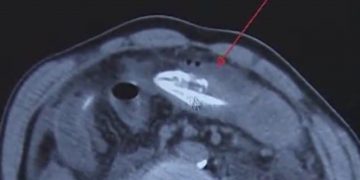

Μπροστά σε ένα απίστευτο περιστατικό βρέθηκαν… οι γιατροί σε νοσοκομείο της Κίνας όταν εμφανίστηκε άνδρας, ο οποίος είχε βάλει ένα τεράστιο χέλι στον πρωκτό του, προκειμένου να «ανακουφιστεί» από τη δυσκοιλιότητα που τον ταλαιπωρούσε.

Τουλάχιστον… αυτό είπε στους γιατρούς, οι οποίοι έμειναν με το στόμα ανοικτό αντικρίζοντας τις πρωτοφανείς εικόνες από την ακτινογραφία.

Σύμφωνα με την dailymail.co.uk πρόκειται για χέλι, μήκους σχεδόν 20 εκατοστών, το οποίο όχι μόνο ήταν ακόμα ακόμα ζωντανό, αλλά κατάφερε να φτάσει μέχρι την κοιλιά του άτυχου άνδρα, ο οποίος λίγο έλειψε να βρει τραγικό θάνατο, αναζητώντας εναλλακτικές ιατρικές θεραπείες.

Σύμφωνα επίσης με τους γιατρούς, το χέλι, το οποίο εξερεύνησε το πιο παράξενο και αφιλόξενο μέρος που έχει βρεθεί ποτέ, δάγκωσε το έντερο του Κινέζου, ο οποίος ισχυρίζεται ότι η θεραπεία που επέλεξε βασίζεται σε ένα παλιό παραδοσιακό γιατροσόφι για την καταπολέμηση των προβλημάτων του παχέος εντέρου.

Σύμφωνα πάντα με το δημοσίευμα, οι γιατροί αφαίρεσαν με χειρουργική επέμβαση το μεγάλο χέλι, το οποίο παρά τις αντίξοες συνθήκες στις οποίες βρέθηκε… επέζησε.

Οι γιατροί προειδοποίησαν πάντως τον άνδρα που δεν δίστασε να πειραματιστεί με κάτι… ζωντανό, μήκους 20 ολόκληρων εκατοστών και τον πρωκτό του, πως ήταν πολύ τυχερός καθώς θα μπορούσε να είχε αφήσει την τελευταία του πνοή